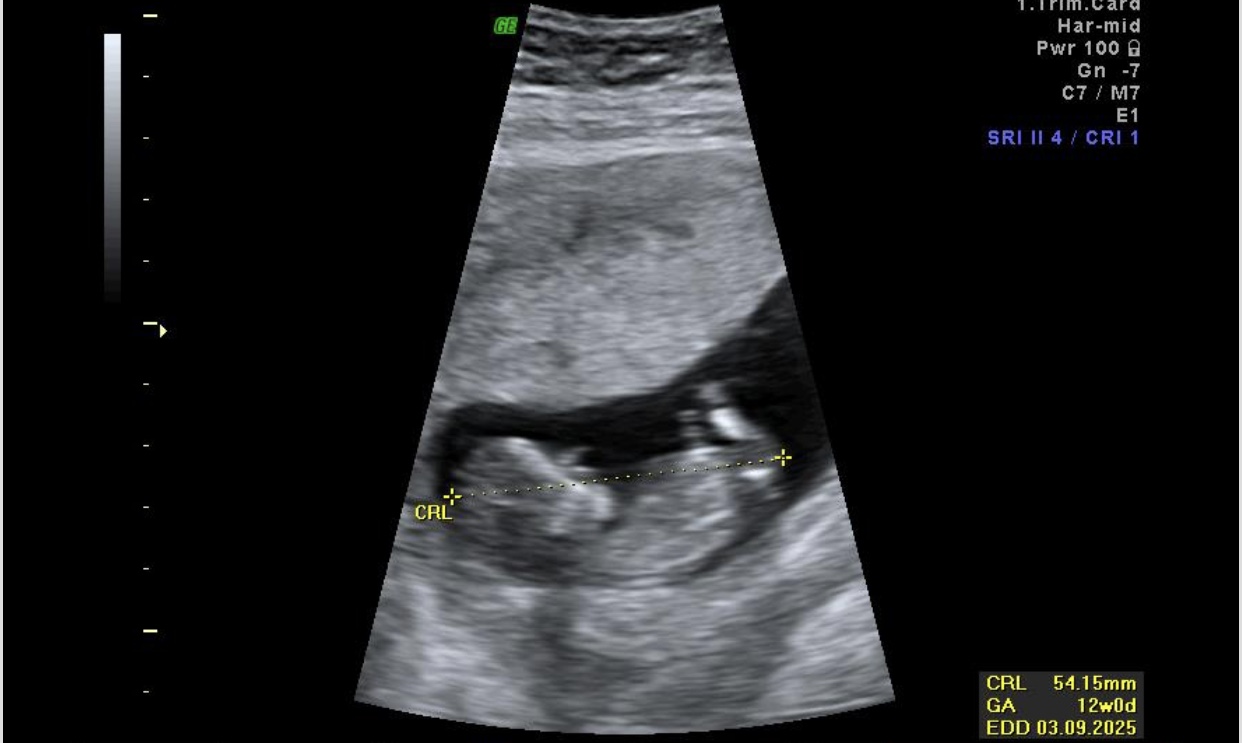

شرمنده که من نمیدونم. اتفاقا خودمم الان سونو ان تی بودم نی نی بلا پاهاشو جمع کرده بود تکونم نمی‌داد. حتی خانم دکتر احتمال چیزی هم نداد.

برای من احتمال دختر داد اما گفت خطا داره قطعی نیست ضربان قلبشم۱۶۷بود

خداروشکر همه چیش خوب بود دختر و پسریش فرقی نداره🥹